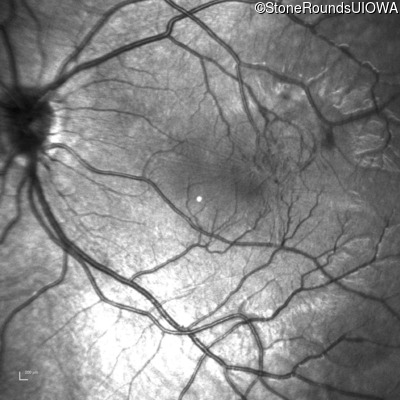

Infrared Fundus Photograph - Left - 20/80

Exemplar